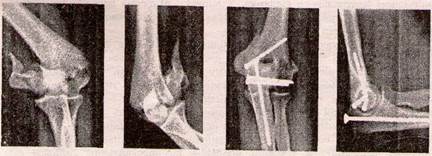

При переломах без зміщення відламків лікування полягає у фіксації ліктьового суглоба задньою гіпсовою шиною від верхньої третини плеча до головок п'ясних кісток при зігнутому до 90° передпліччі в положенні напівпронації терміном на 4-5 тижнів. У випадку зміщення відламків проводять закриту репозицію під місцевим чи загальним знеболенням і фіксацію в глибокій задній гіпсовій шині. Неможливость закритої репозиції відламків чи вторинне їх зміщення та неможливость відновлення конгруент­ності суглобових поверхонь є показанням до оперативного лікування — відкритої репозиції та фіксаціії відламків компресувальним гвинтом або спицями Кіршнера (рис. 13).

Рисунок 13 — Перелом зовнішнього виростка плечової кістки до та після операції

Аналогічна лікувальна тактика при переломі внутрішнього виростка (рис. 14).

Фронтальні переломи у всіх випадках потребують відкритої репозиції та остеосинтезу в напрямку проведення гвинтів чи спиць ззаду - спереду.

Рисунок 14 - Перелом внутрішнього виростка плечової кістки до та після операції

Для остеосинтезу Т- і У-подібних переломів виростка плечової кістки використовують методики Кемпбелла, Лангенбека. При цьому для співстав-лення відламків часто виконують остеотомію ліктьового відростка з наступним його остеосинтЛом гвинтом (рис. 15).

Рисунок 15 - Перелом виростків плечової кістки до та після операції

У випадку Т-подібного перелому, де горизонтальна площина зламу проходить вище виростка, у дорослих для остеосинтезу використовують реконструктивні пластини по медіальному і латеральному краю дистального метаепіфізу плечової кістки (рис. 16).

Рисунок 16 - Т-подібний перелом виростків плечової кістки до та після операції